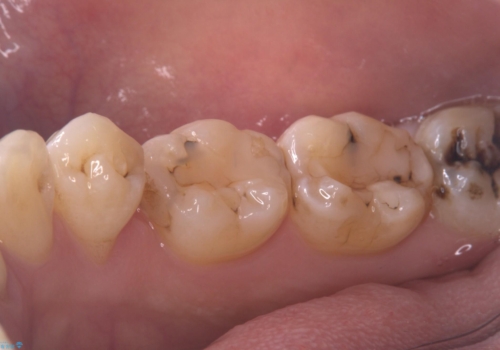

- 主訴:詰め物と歯の奥が側の境目に物がいつも溜まってしまう

保険適応のメタルインレーと歯質との間に不適合な箇所を認め、補綴物のやり替えでの治療となりました。インレーからクラウンへ補綴物の形態を変更し、素材は清掃性・適合性・審美性の点からセラミッククラウンでのやり替となりました。

レントゲン上にて、左上6番遠心にインレーと歯質の不適合を認めます。

健全歯質の残存量から、クラウンでのやり替えを提案しオールセラミッククラウン(スタンダード)でのやり替えとなりました。